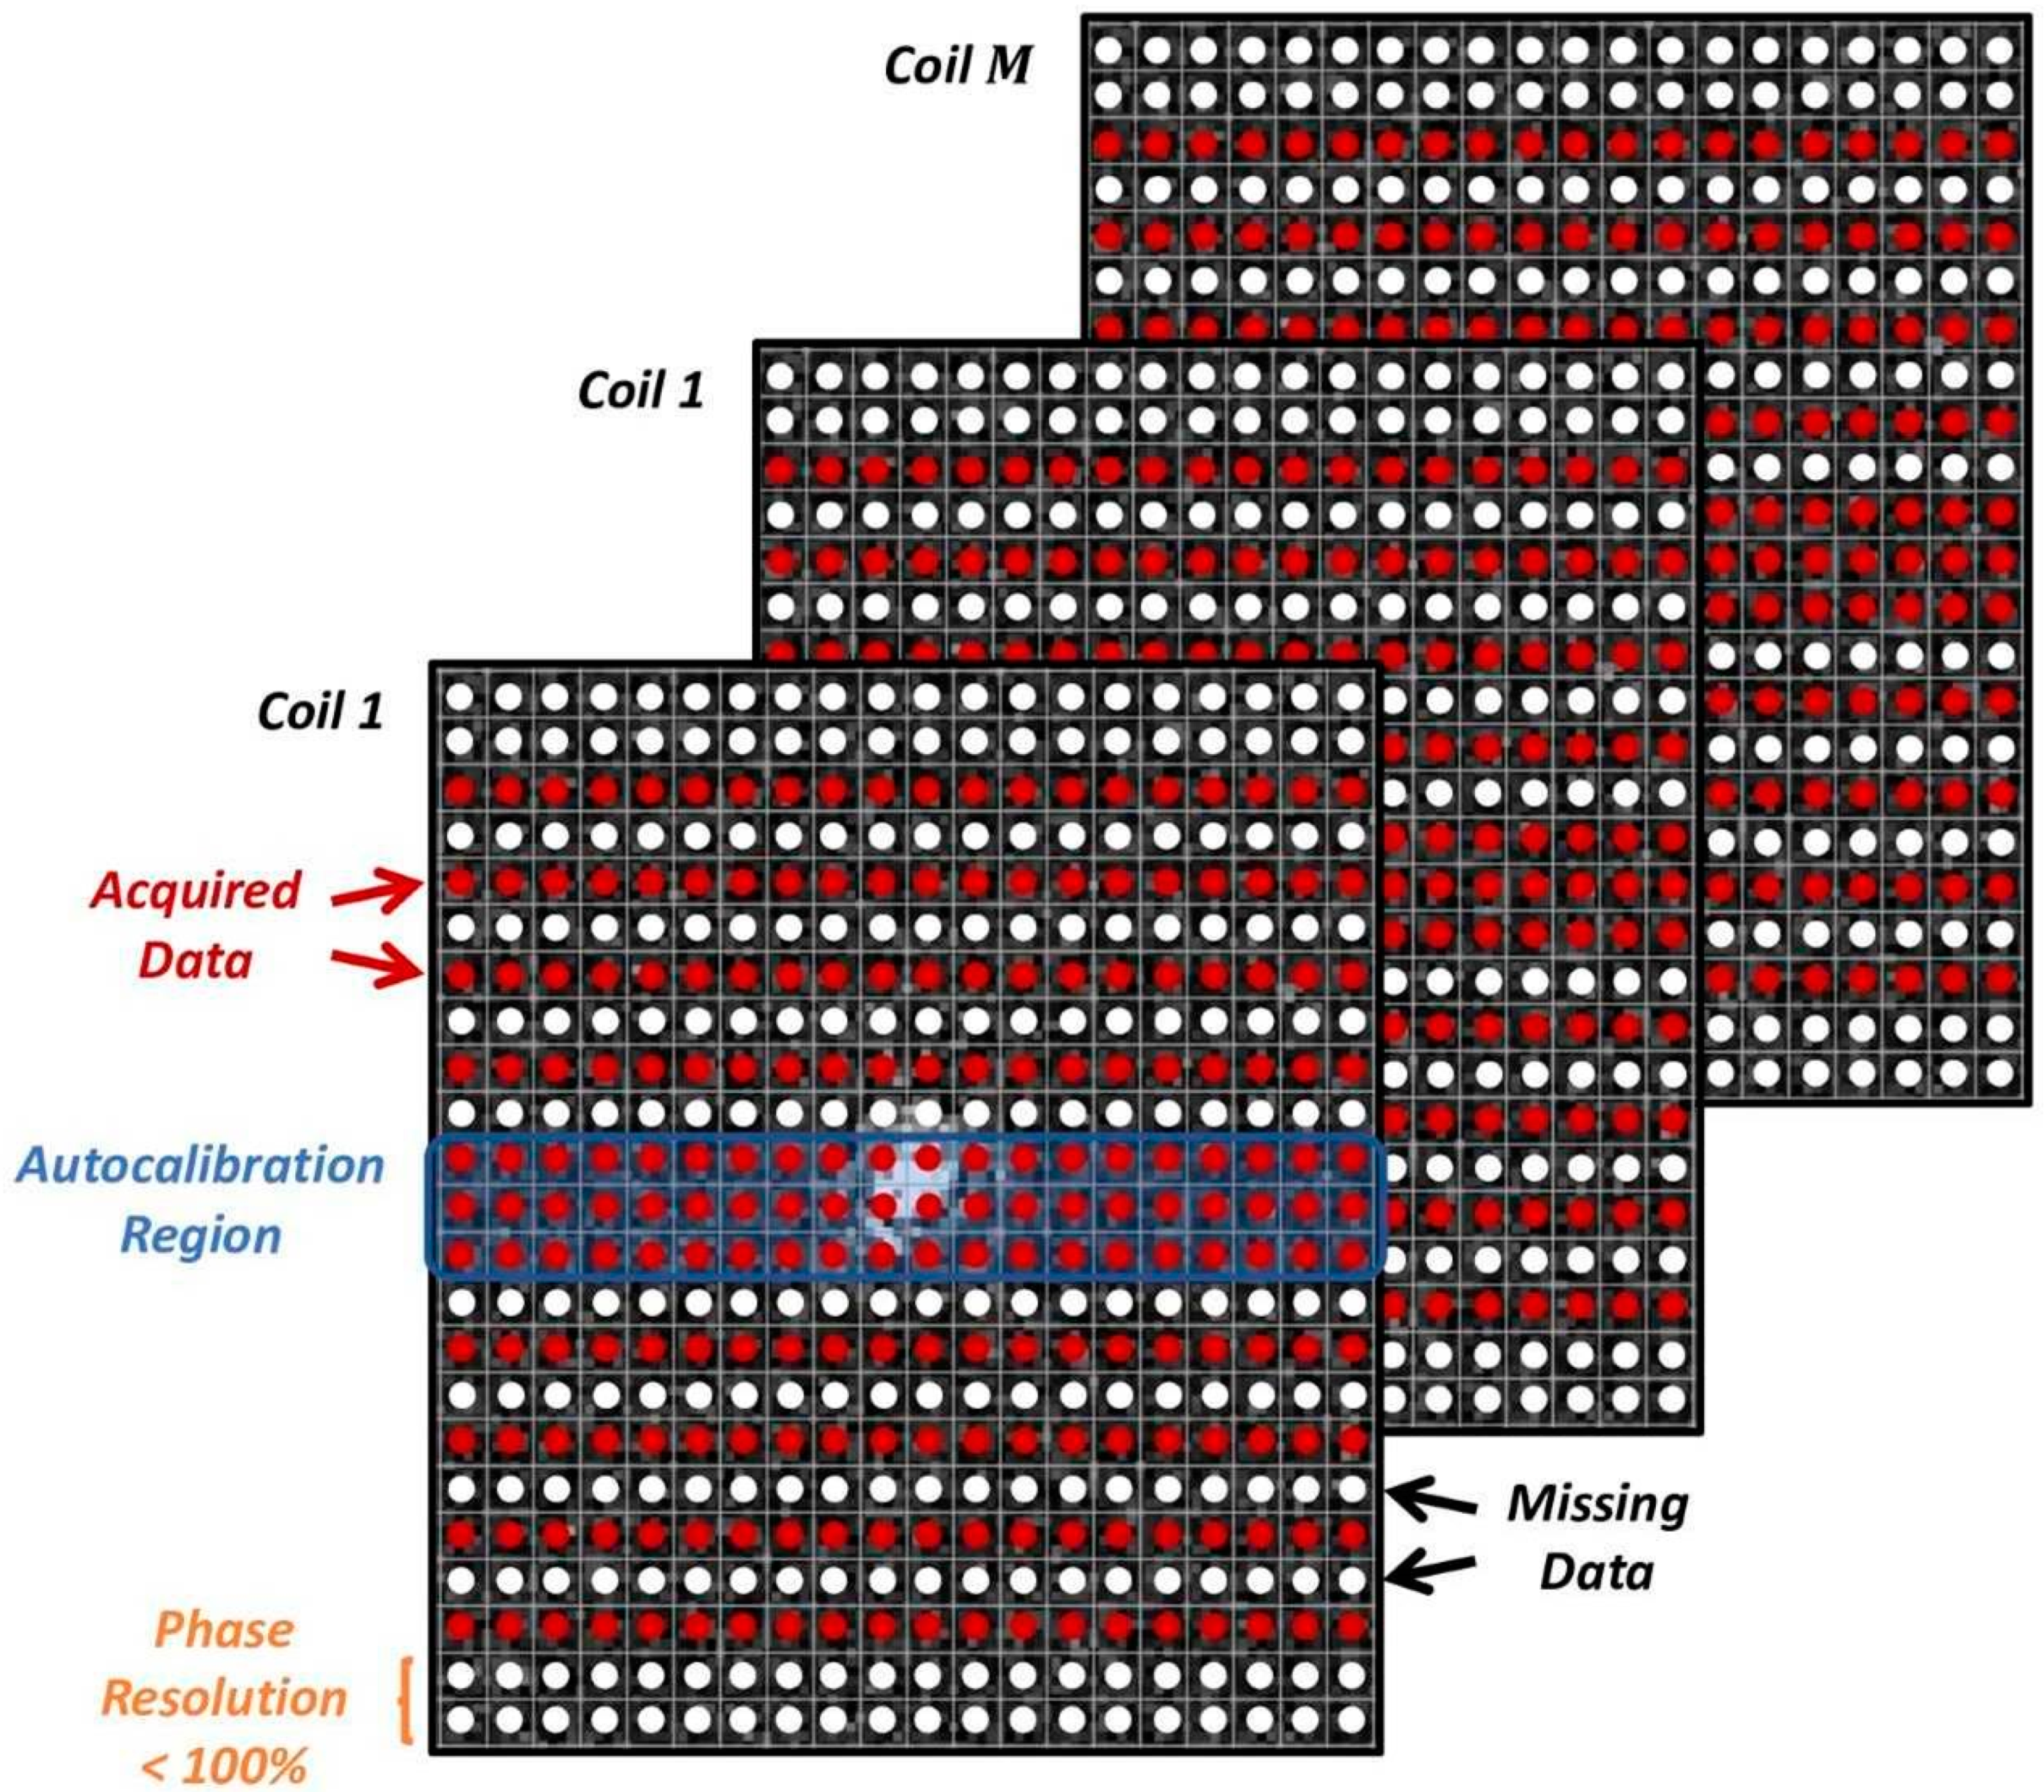

2.2. Deep Learning Image Reconstruction

2.3. Implementation of DL Image Reconstruction in Clinical Workflow